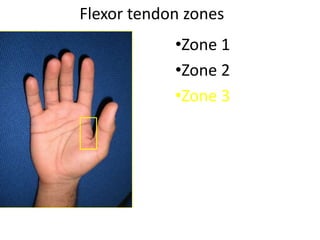

- It describes flexor tendon zones, extensor compartments, and pulley system anatomy.